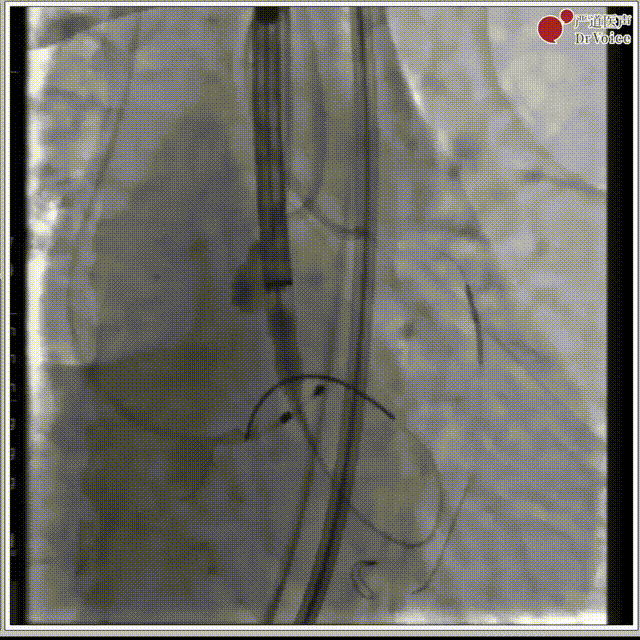

2. 冠脉保护,左冠预埋支架。

冠脉保护后造影

3. 18mm球囊预扩,有明显腰征,冠脉无遮挡,无瓣周漏。

球囊预扩